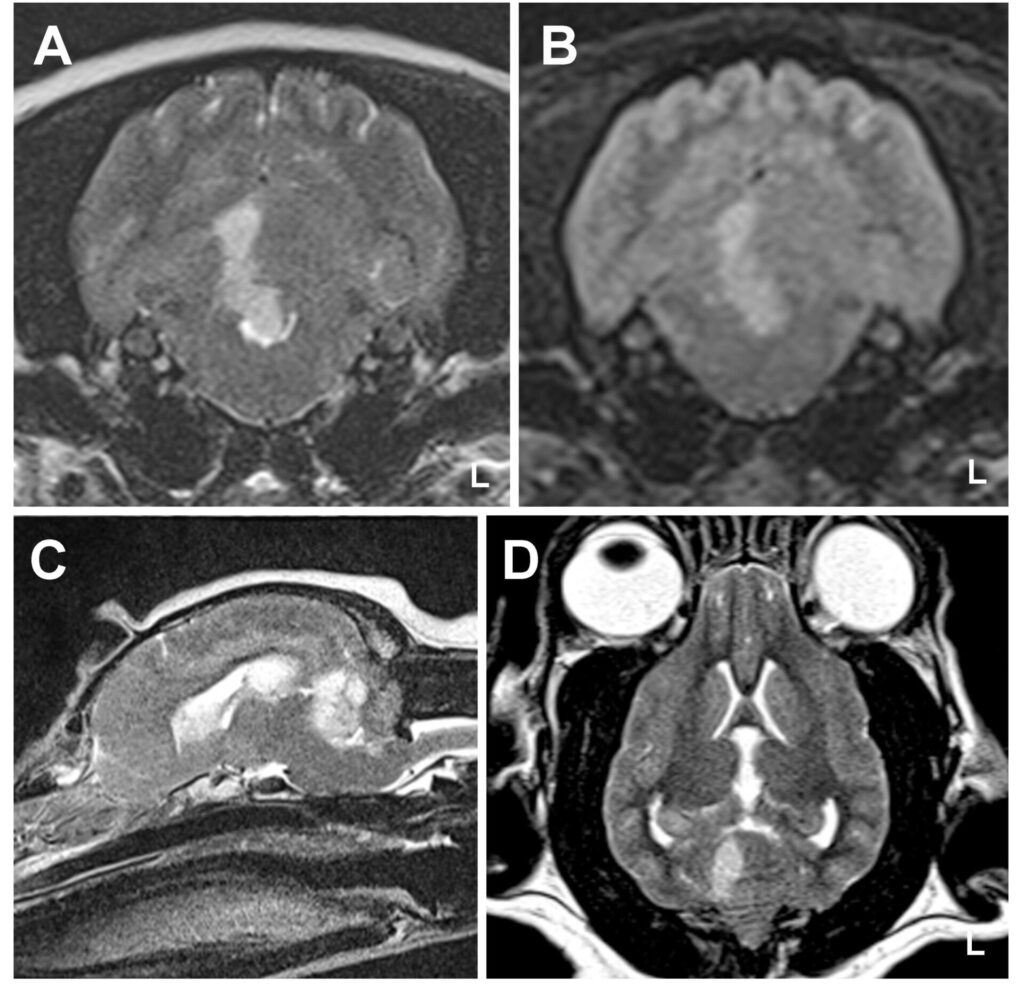

You may suspect that the patient has suffered a stroke based on the signs they are showing. Further tests, including brain imaging, will be needed to make a definite diagnosis. MRI (magnetic resonance imaging) scans can give an inside view of the brain (see caudal perforating artery image and borderzone infarct image on MRI). This diagnosis cannot be made with standard X-rays. As part of these tests, the pet will be anaesthetized, and a spinal fluid sample will be taken to check for other diseases that may cause similar signs.